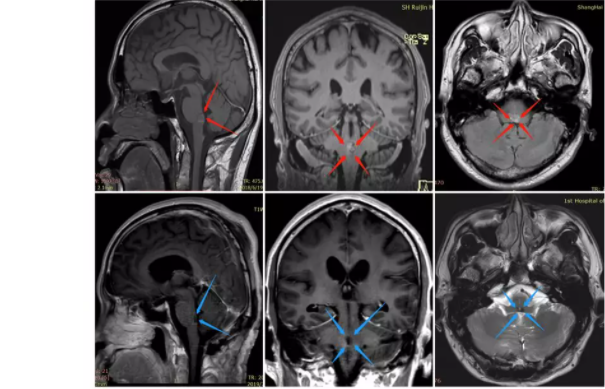

中脑背侧胶质瘤